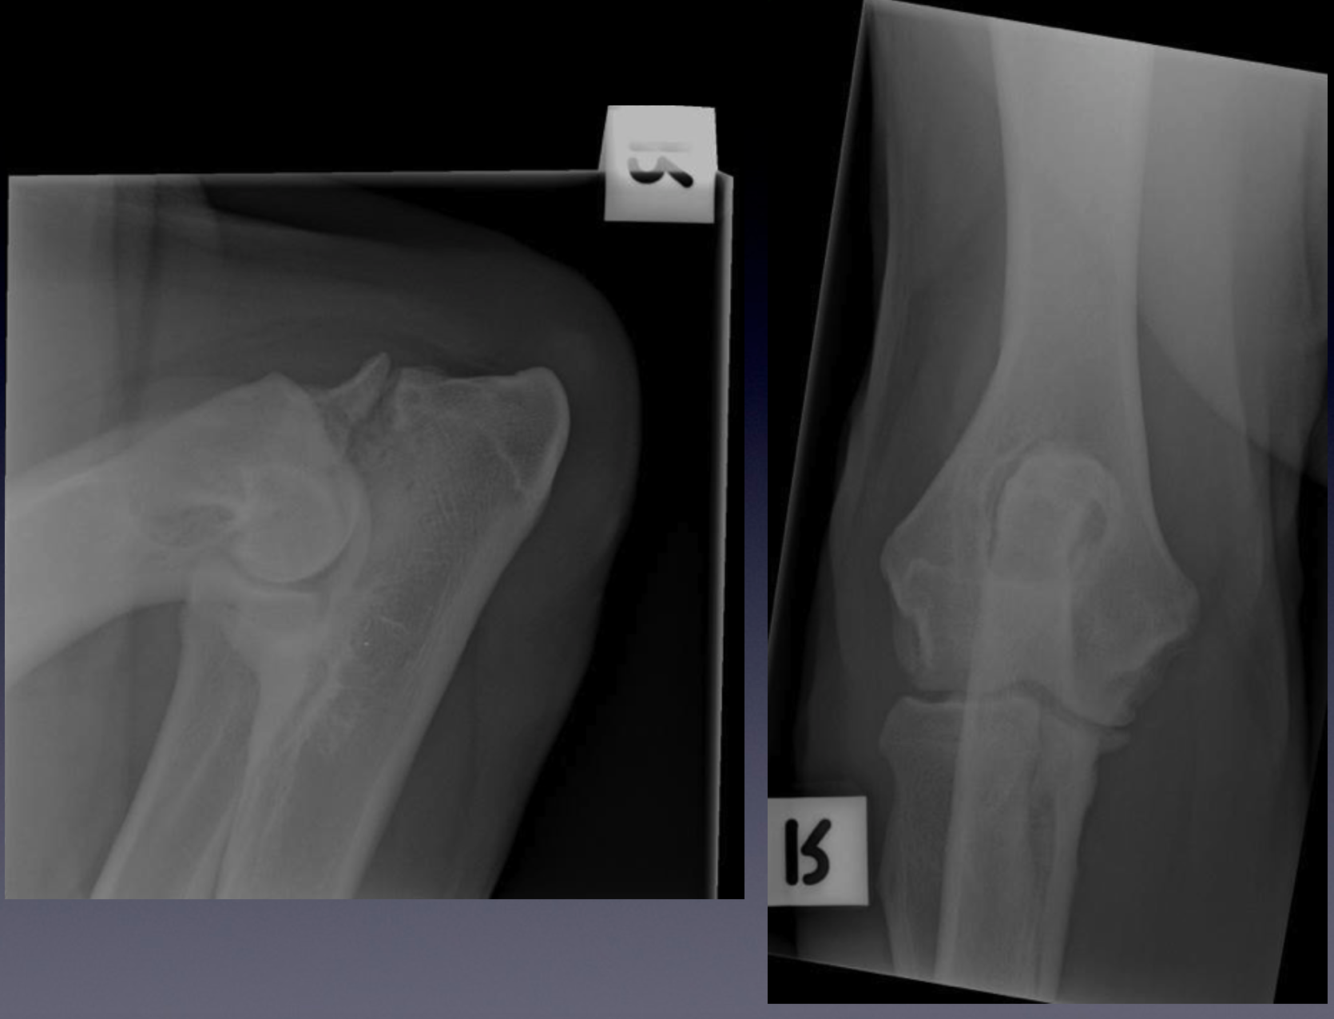

Case 6: Patient 237244

VIEW?

Compare these radiographs to the example of a normal elbow.

The irregular radiolucent line separating the anconeal process from the olecranon. This is

called an ununited anconeal process.

sclerosis at the base of the medial coronoid process of the ulna

irregular border to the medial coronoid process, as seen on the craniocaudal view

osteophyte formation along the proximal contour of the anconeal process

sclerosis of the ulna trochlear notch

Ununited anconeal process is one of the causes of elbow dysplasia. What are the other

potential causes of elbow dysplasia? What is the expected sequela of elbow dysplasia?

Flexed mediolateral and craniocaudal projections of the elbow of a dog.